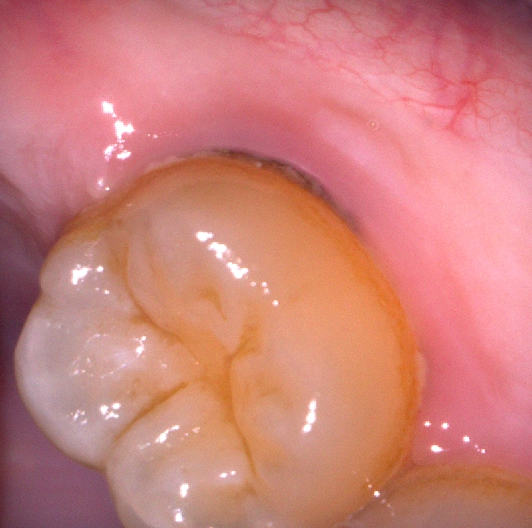

잇몸사이에 나있는 회색 줄같은거 혹시 충치인가요?

충치같이 보이긴 하는데 충치면 빨리 치료해야할거같아서요 아픈느낌은 없지만

사진으로 판단이 힘들수도 있겠지만 확인 부탁드려요

치석이 있는 것으로 보아 잇몸염증 등도 의심됩니다. 충치의 양상과는 조금 다르며 치과는 가보시는 게 좋겠습니다.

치석도 저렇게 보이기도 합니다 뿌리충치이거나 아니면 치석일 것 같습니다 다만 찬물에 시린 증상이 평상시 없었다면 치석일 확률이 큽니다

충치일 가능성 보다 치석일 가능성이 높습니다. 원래 치아와 잇몸 경계부에 치석이 잘 낍니다.

치석이 쌓여서 그럴수도 있으니 치과에 가셔서 스켈링 및 잇몸치료를 받아보시는게 좋을것같습니다.